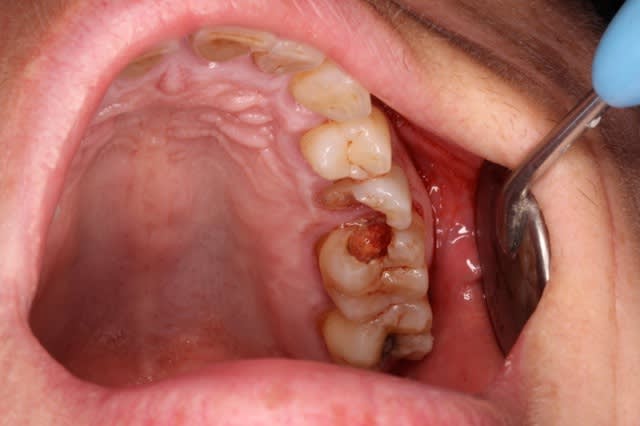

Moi aussi rassures toi je ré interviens tout le temps. Tu fais quoi dans ce cas là : patient CMU qui veut remplacer la 46 et la 36 ? Attention IL veut les remplacer ca ne vient pas de moi je ne lui ai pas fait du rentre dedans. ( 46 a été extraite). Je fais les RTE ou pas sur 37, 47 ?

Tu lui fais un détartrage parce que ca compte plus qu'une consult tu lui fais un devis pour 2 implants pour qu'il aille se faire F..... ailleurs ? Ou alors les CMUS sont filtrés avant au secrétariat avant d'arriver sur le fauteuil du DR spécialiste es no post no crown ?